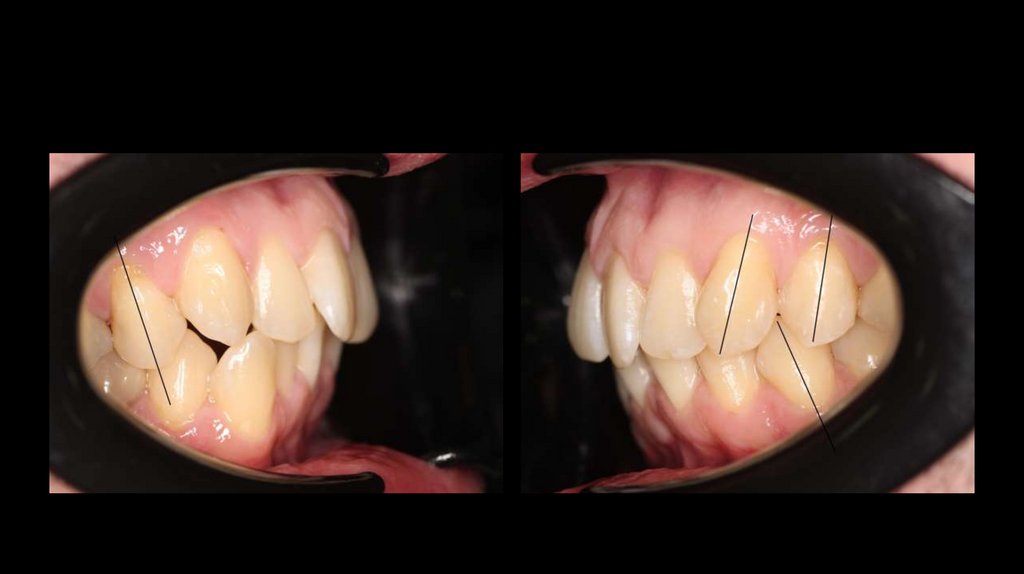

6. Внутриротовые фото

Избыточная небная инклинация жевательных зубов.

Центры верхнего и нижнего зубных рядов совпадают.

7.

Наличие рецессий десны 1.6-1.4, 2.4-2.6, 3.7-3.4, 4.3-4.6

8.